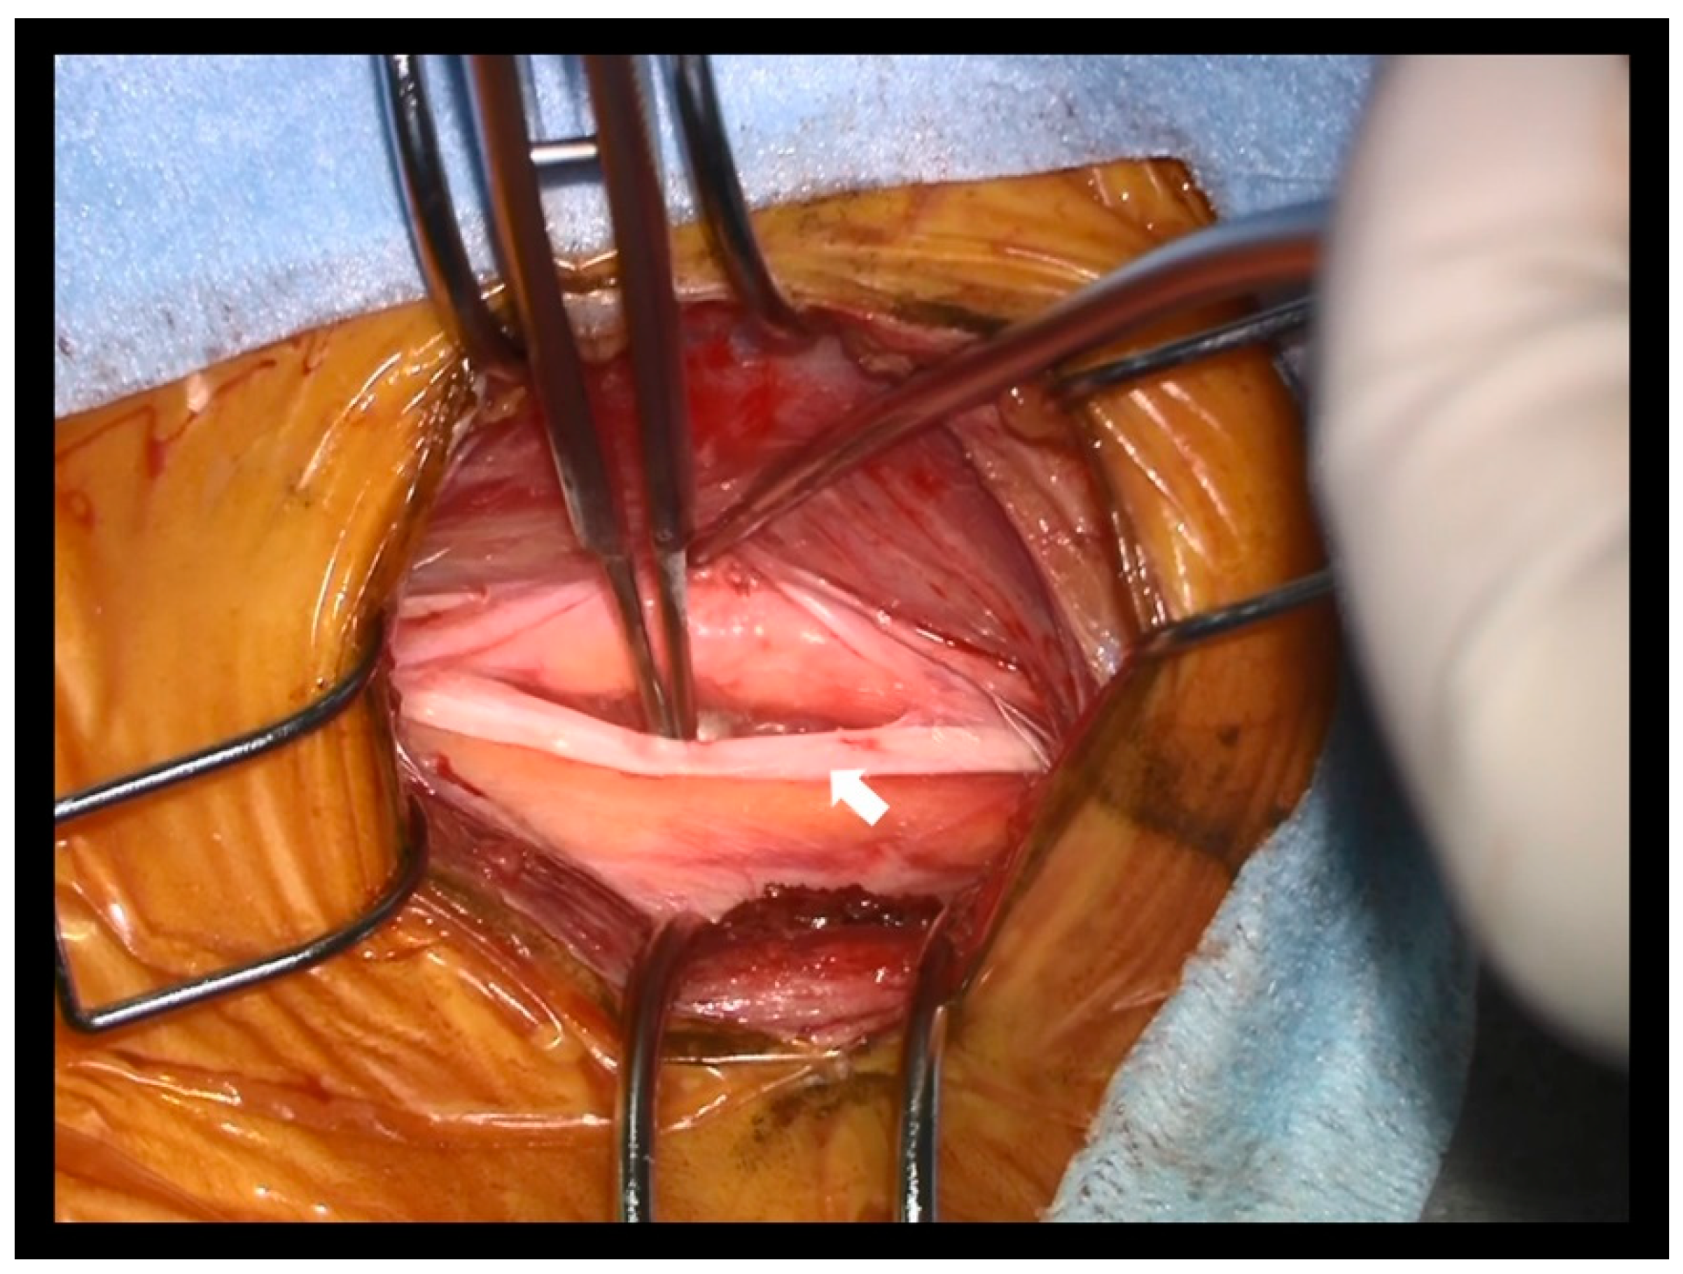

Figure 4.

The intraoperative picture in case 1. The vagus nerve was detected by laterally pulling the IJV as the authors preoperatively predicted (arrow). The white arrow indicates the vagus nerve.

In both cases, the vagus nerve was identified after pulling the IJV (Figure 4). The vagus nerve was confirmed by direct stimulation using the NIM TriVantage EMG. The time from the beginning of the surgery until vagus nerve detection was 47 min and 54 min in cases 1 and 2, respectively. In both cases, the surgery was completed without any complications.